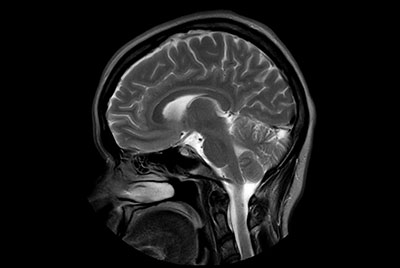

Brain overview